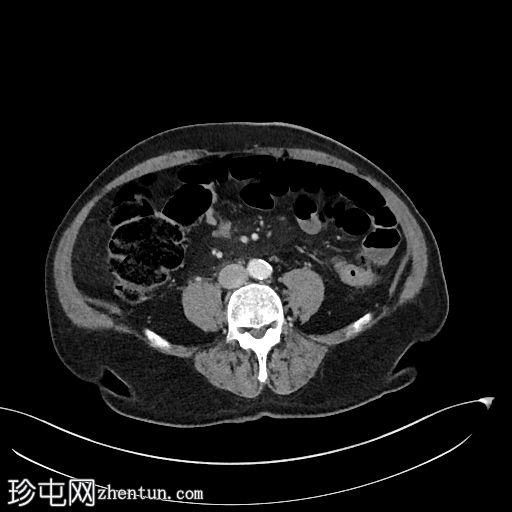

冠状位增强扫描(门静脉期)

2.jpg

可见胆道支架位置良好,管腔内可见分层气液平面。支架远端位于充满液体的D2段内。支架内未见明显放射性结石。

肝内胆管未扩张,但可见胆道积气。

胰头水肿,伴胰周脂肪浸润。未见明显积液。

胰头局灶性结节(代表已知的肿瘤),伴有上游主胰管扩张,位于萎缩的胰颈、胰体和胰尾内。背景可见胰腺实质内钙化。